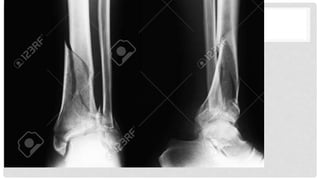

Fracturas del pilón tibial

Patoanatomía

se caracteriza por

- Impactación articular y trituración hueso metafisario

- Lesión de tejidos blandos ( abierta o tscherne II / III

fracturas cerradas)

- Asociados lesiones musculoesqueléticas

- 3 fragmentos típicos con los ligamentos del tobillo

intactas

- Maléolo medial (ligamento deltoideo)

- Posterolateral / fragmento de Volkmann (inferior

posterior del ligamento tibio-peroneo)

- Anterolateral / fragmento de Chaput (ligamento

tibio-peroneo inferior)

condiciones asociadas

• 75% han asociado fracturas peroné